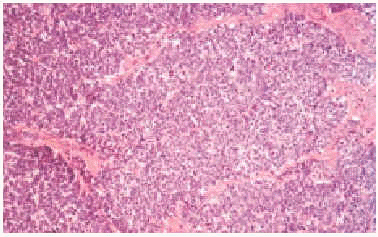

Histológicamente mostraron una disposición dérmica en sábanas o racimos que afectaba a epidermis, en algunos casos. Se registraron 2 casos de invasión linfática. En la mayoría de los casos el tumor estaba formado por pequeñas células basófilas con núcleo redondo y vesicular con cromatina dispersa y nucléolos pequeños periféricos junto con escaso citoplasma (figs. 2 y 3). Las figuras mitóticas fueron en todos los casos muy notables, acompañadas por fenómenos de apoptosis. El estroma presentaba proliferación vascular en forma de fino entramado capilar con endotelios reactivos. En uno de los casos (paciente 2), la histología presentó características peculiares con un patrón epitelioide fusocelular y disposición en trabéculas.

Fig. 3.--Patrón histológico del carcinoma de células de Merkel (HE, x200).